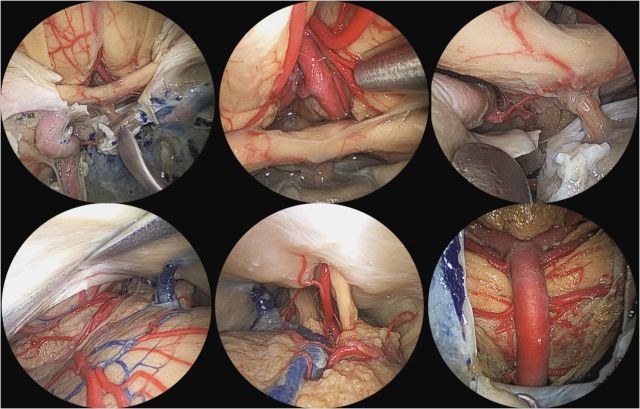

坐位听神经瘤切除术视频(摘自鲍教授上述讲课)

鲍遇海教授:坐位听神经瘤切除术